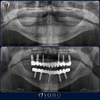

علاج تسوس الاسنان

الصور